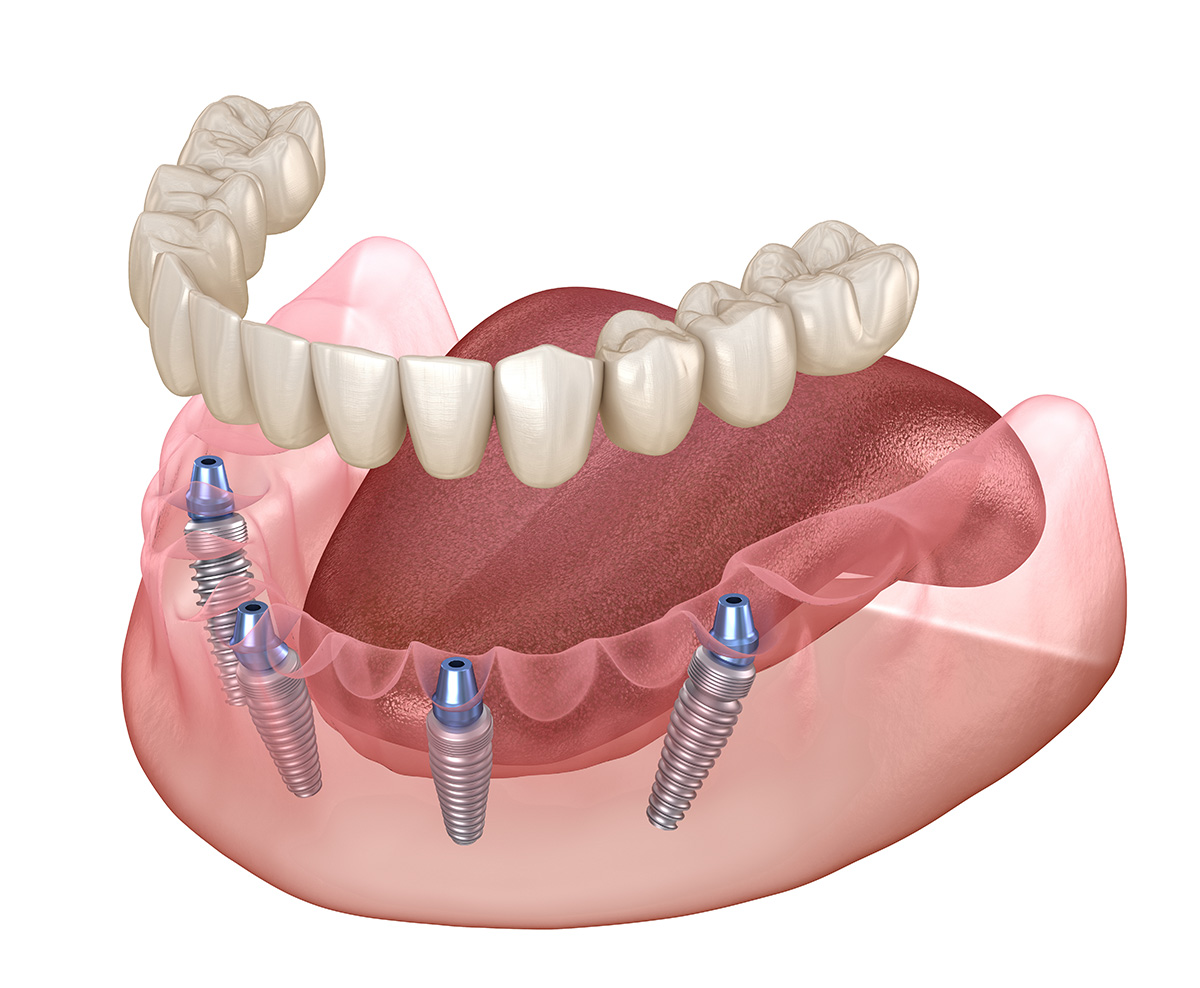

Les systèmes All-on-4 et All-on-6 offrent une solution avancée pour les patients édentés souhaitant retrouver un sourire fonctionnel et esthétique. Ces techniques innovantes consistent à placer quatre à six implants dentaires stratégiquement dans la mâchoire afin de supporter une prothèse dentaire fixe.

Contrairement aux solutions traditionnelles, ces systèmes permettent une réhabilitation complète en une seule intervention, avec une prothèse provisoire posée immédiatement après l’opération.

Pour garantir un positionnement optimal des implants et une stabilité à long terme, la chirurgie guidée joue un rôle essentiel. Cette technique repose sur un plan de traitement numérique détaillé, élaboré à partir d’un scanner 3D et d’une modélisation informatique.

Une fois le positionnement des implants déterminé avec précision, un guide chirurgical est imprimé en 3D pour assurer une insertion idéale des implants. Cela permet de réduire les risques, d’améliorer le confort post-opératoire et d’optimiser la durée de cicatrisation.